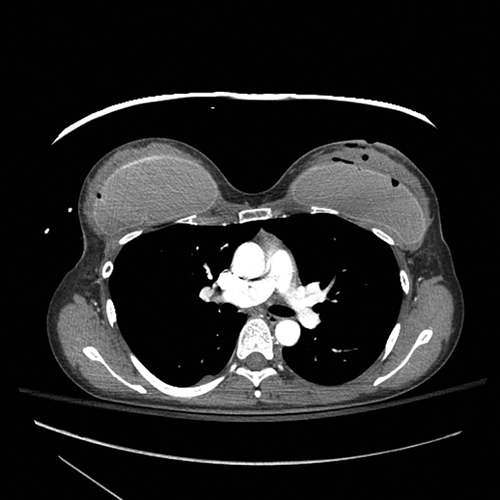

НемедицинаПосле операции был проведен баллистический анализ с использованием спиральной аксиальной компьютерной томографии ( фото 7 – 9)

Figure 7. Аксиальная компьютерная томография (КТ) выявила входное отверстие в левой молочной железы с пулевым ходом в левом грудном имплантате, гематому и повреждение мягких тканей.